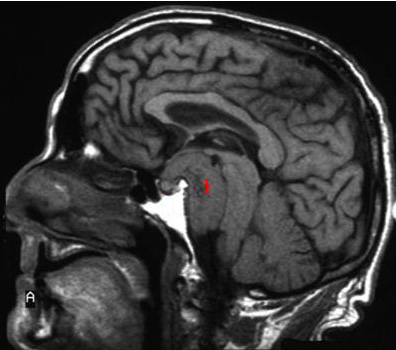

MR uden kontrast - sagitalt snit

1. Meningeomet (bindevævsknude udgående fra hjernehinde)